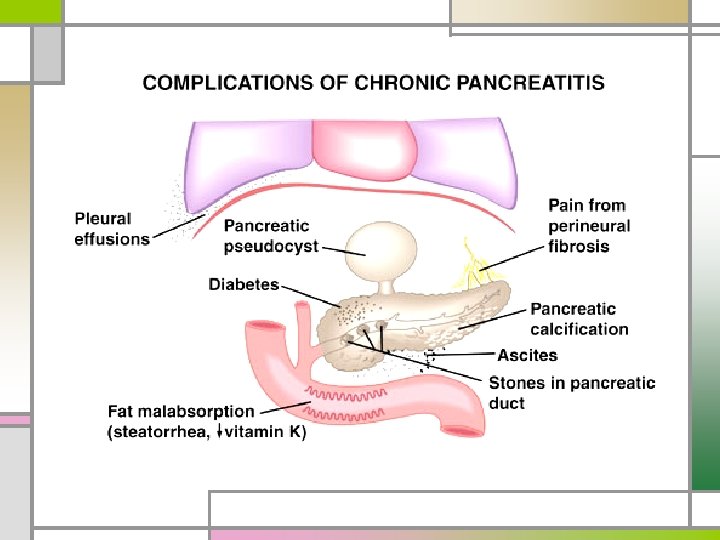

Chronic Pancreatitis calcification Pancreatic duct dilatation and stones

Clinical Features n Relapsing chronic pancreatitis - pain identical to those of acute pancreatitis - continuous, intermittent, or absent n Abdominal pain - persistent, deep-seated, & unresponsive to antacids - worsened by ingestion of alcohol or a heavy meal - pathogenesis: poorly understood. n Weight loss, abnormal stools, signs or symptoms of malabsorption Chronic Pancreatitis

Diagnostic Evaluation n Serum amylase & lipase - usually not elevated n Abnormal liver function tests n Impaired glucose tolerance, excretion of fecal fat n Triad : calcification, steatorrhea, diabetes mellitus - less than one-third - established the diagnosis of chronic pancreatitis - secretin stimulation test (+) Chronic Pancreatitis

n Pancreas calcification n Alcohol n Severe protein-calorie malnutrition n Hereditary pancreatitis n Post-traumatic pancreatitis n Hyperparathyroidism n Islet cell tumors n Idiopathic chronic pancreatitis Decrease or disappear spontaneously in 1/3 case (dynamic process) Chronic Pancreatitis

n Cobalamin (vitamin B 12) - excessive binding of cobalamin by cobalaminbinding proteins other than IF - Tx: pancreatic enzyme (proteases) n Impaired glucose tolerance - uncommon DKA, coma, end organ failure n Nondiabetic retinopathy - vitamin A, zinc deficiency Chronic Pancreatitis

n Gastrointestinal bleeding - peptic ulceration, gastritis - pseudocyst eroding into the duodenum - ruptured varices secondary to splenic vein thrombosis n Icterus - edema of the head of the pancreas, compressing the CBD - chronic cholestasis (inflammation around intrapancreatic bile duct) n Pancreatic carcinoma n Addiction to narcotics - most common and troublesome complication Chronic Pancreatitis